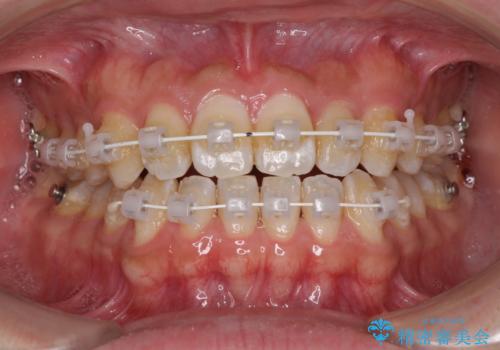

- 矯正装置

- 審美装置

- 1年

- 10-30回